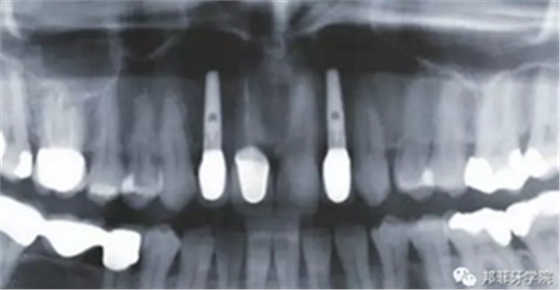

26歲女性患者,雙側(cè)上頜側(cè)切牙先天缺失,對(duì)原有修復(fù)體的“形態(tài)”、“光澤”等方面不滿意,希望重新修復(fù)(圖1&2)。12及22原為粘接橋修復(fù),11根管治療史;拆除原修復(fù)體后余鄰牙完整,未見病理性探診深度。無系統(tǒng)疾病史。患者期望值較高,告知治療流程佩戴臨時(shí)卡環(huán)義齒等(圖3)、費(fèi)用、風(fēng)險(xiǎn)后表示接受治療。

圖2:治療前全景片